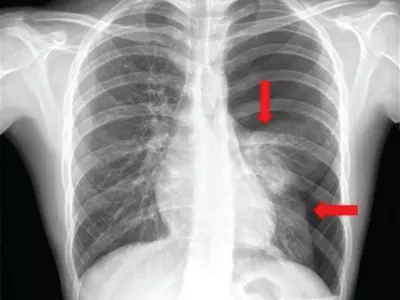

■ 황유화 분당서울대병원 흉뷰외과 교수흉부 X선 검사에 나타난 기흉.# 고3 남학생 A군은 키가 크고 마른 체형이다. A군은 모의..